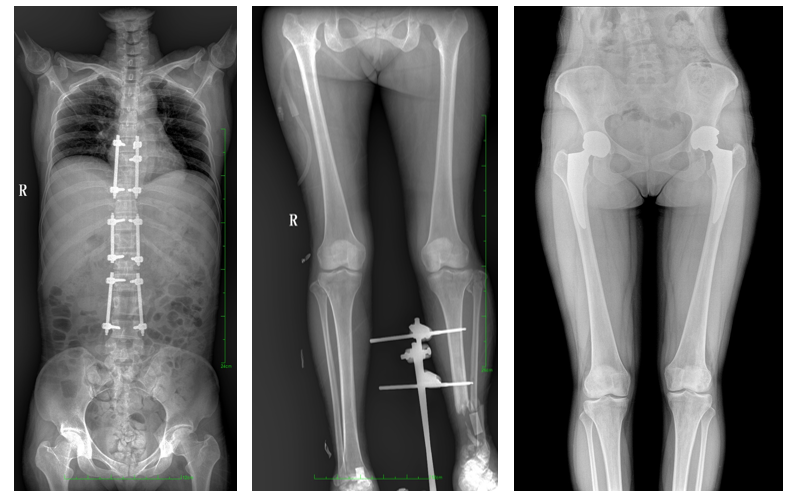

站立位X線影像是測定人體負重骨骼的生物學力線、對稱結構平滑線及脊柱側凸角等首選的檢查內容,這和CT、MRI臥位成像,在臨床意義上有著根本區別。在脊柱及下肢的臨床治療過程中,一般需要進行矯正和關節置換手術治療,在對其進行手術前后,均需要拍攝站立位負重X光片以便分析病情,明確診斷和觀察治療效果。

常規DR拍攝面積有限,最大規格僅有43cm,但成人男性全脊柱長度平均為70-75cm,女性為66-70cm,而雙下肢更長。普愛醫療PLX8600動態DR的43cm*86cm超大有效視野,可一次成像全脊柱及雙下肢。